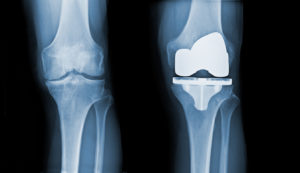

Total Knee Arthroplasty (TKA), also known as total knee replacement, is an orthopedic surgical procedure performed on the knee. TKA is a treatment option for those with a worn-out knee joint, one of the most common causes of which is the wear and tear associated with arthritis. When a TKA is performed, the defective cartilage is removed between the joint, the ends of the bones that meet at the joint are reshaped and fitted with metal implants, and a plastic piece called a spacer is put in [Read More]